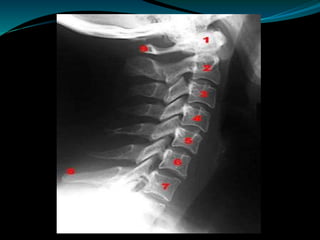

Rx de perfil:

A: Alineación

Tres líneas lordóticas:

Por el borde anterior del cuerpo vertebral

Por el borde posterior del cuerpo vertebral

Por la base de las apófisis espinosas

B: Bone: huesos

Cuerpos vertebrales rectangulares con láminas y

apófisis espinosas unidas a ellos

Las altura anterior del cuerpo no debe diferir en

más de 3 mm de la altura posterior

TRAUMA RAQUIMEDULAR

C: Cartílagos/espacio intervertebral: discos

Espacios uniformes en alto y largo

S: Soft: partes blandas

El área prevertebral(espacio retrofaríngeo)

de C1 a C4 no debe exceder los 7 mm,

de C5 a T1 los 22 mm.

El espacio predental no debe exceder de 3mm